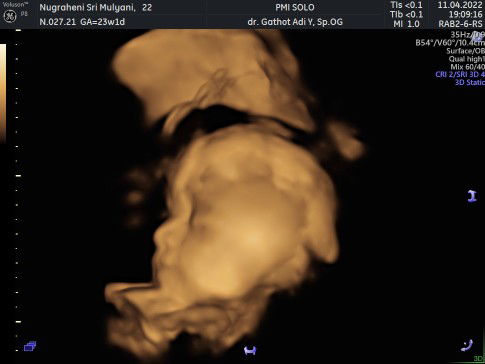

Di PMI Solo ada klinik kandungan. Ada dr obsgyn dan hasil usg nya tp belum termasuk obat ya. Harga tersebut habis naik 20rb per USG.